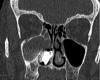

A woman in her late 70s with chronic bilateral epiphora under ophthalmology review was referred to our department for dacryocystorhinostomy after punctoplasty and detection of nasolacrimal duct obstruction. A CT scan of the paranasal sinuses for preoperative planning revealed complete opacification of the right maxillary, anterior ethmoid, frontal and sphenoid sinuses, left septal deviation and an incidental finding of foreign bodies in the right anterior nasal airspace. She proceeded with functional endoscopic sinus surgery (FESS) and removal of foreign bodies. To our surprise, a partially eroded 20 pence and 1 penny coin were found and removed from her right nasal airway. There was no history given about foreign bodies in her nose. Her symptoms improved postoperatively.